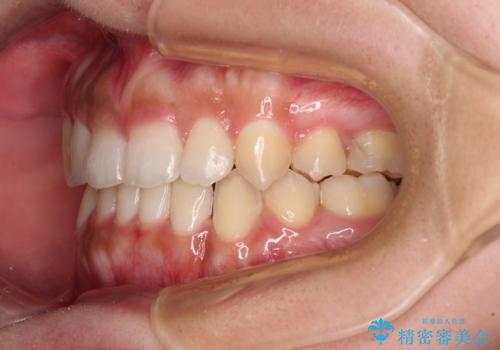

著しい八重歯が気になる インビザラインでの矯正治療

- 顕著な八重歯が気になるとのことで来院された患者様です。

インビザラインでの治療を希望されましたが、インビザライン単独では困難と判断されたため、補助装置や一部ワイヤー装置を用いて行うこととしました。

叢生が強いため、上下左右第一小臼歯4本を抜歯することとしました。